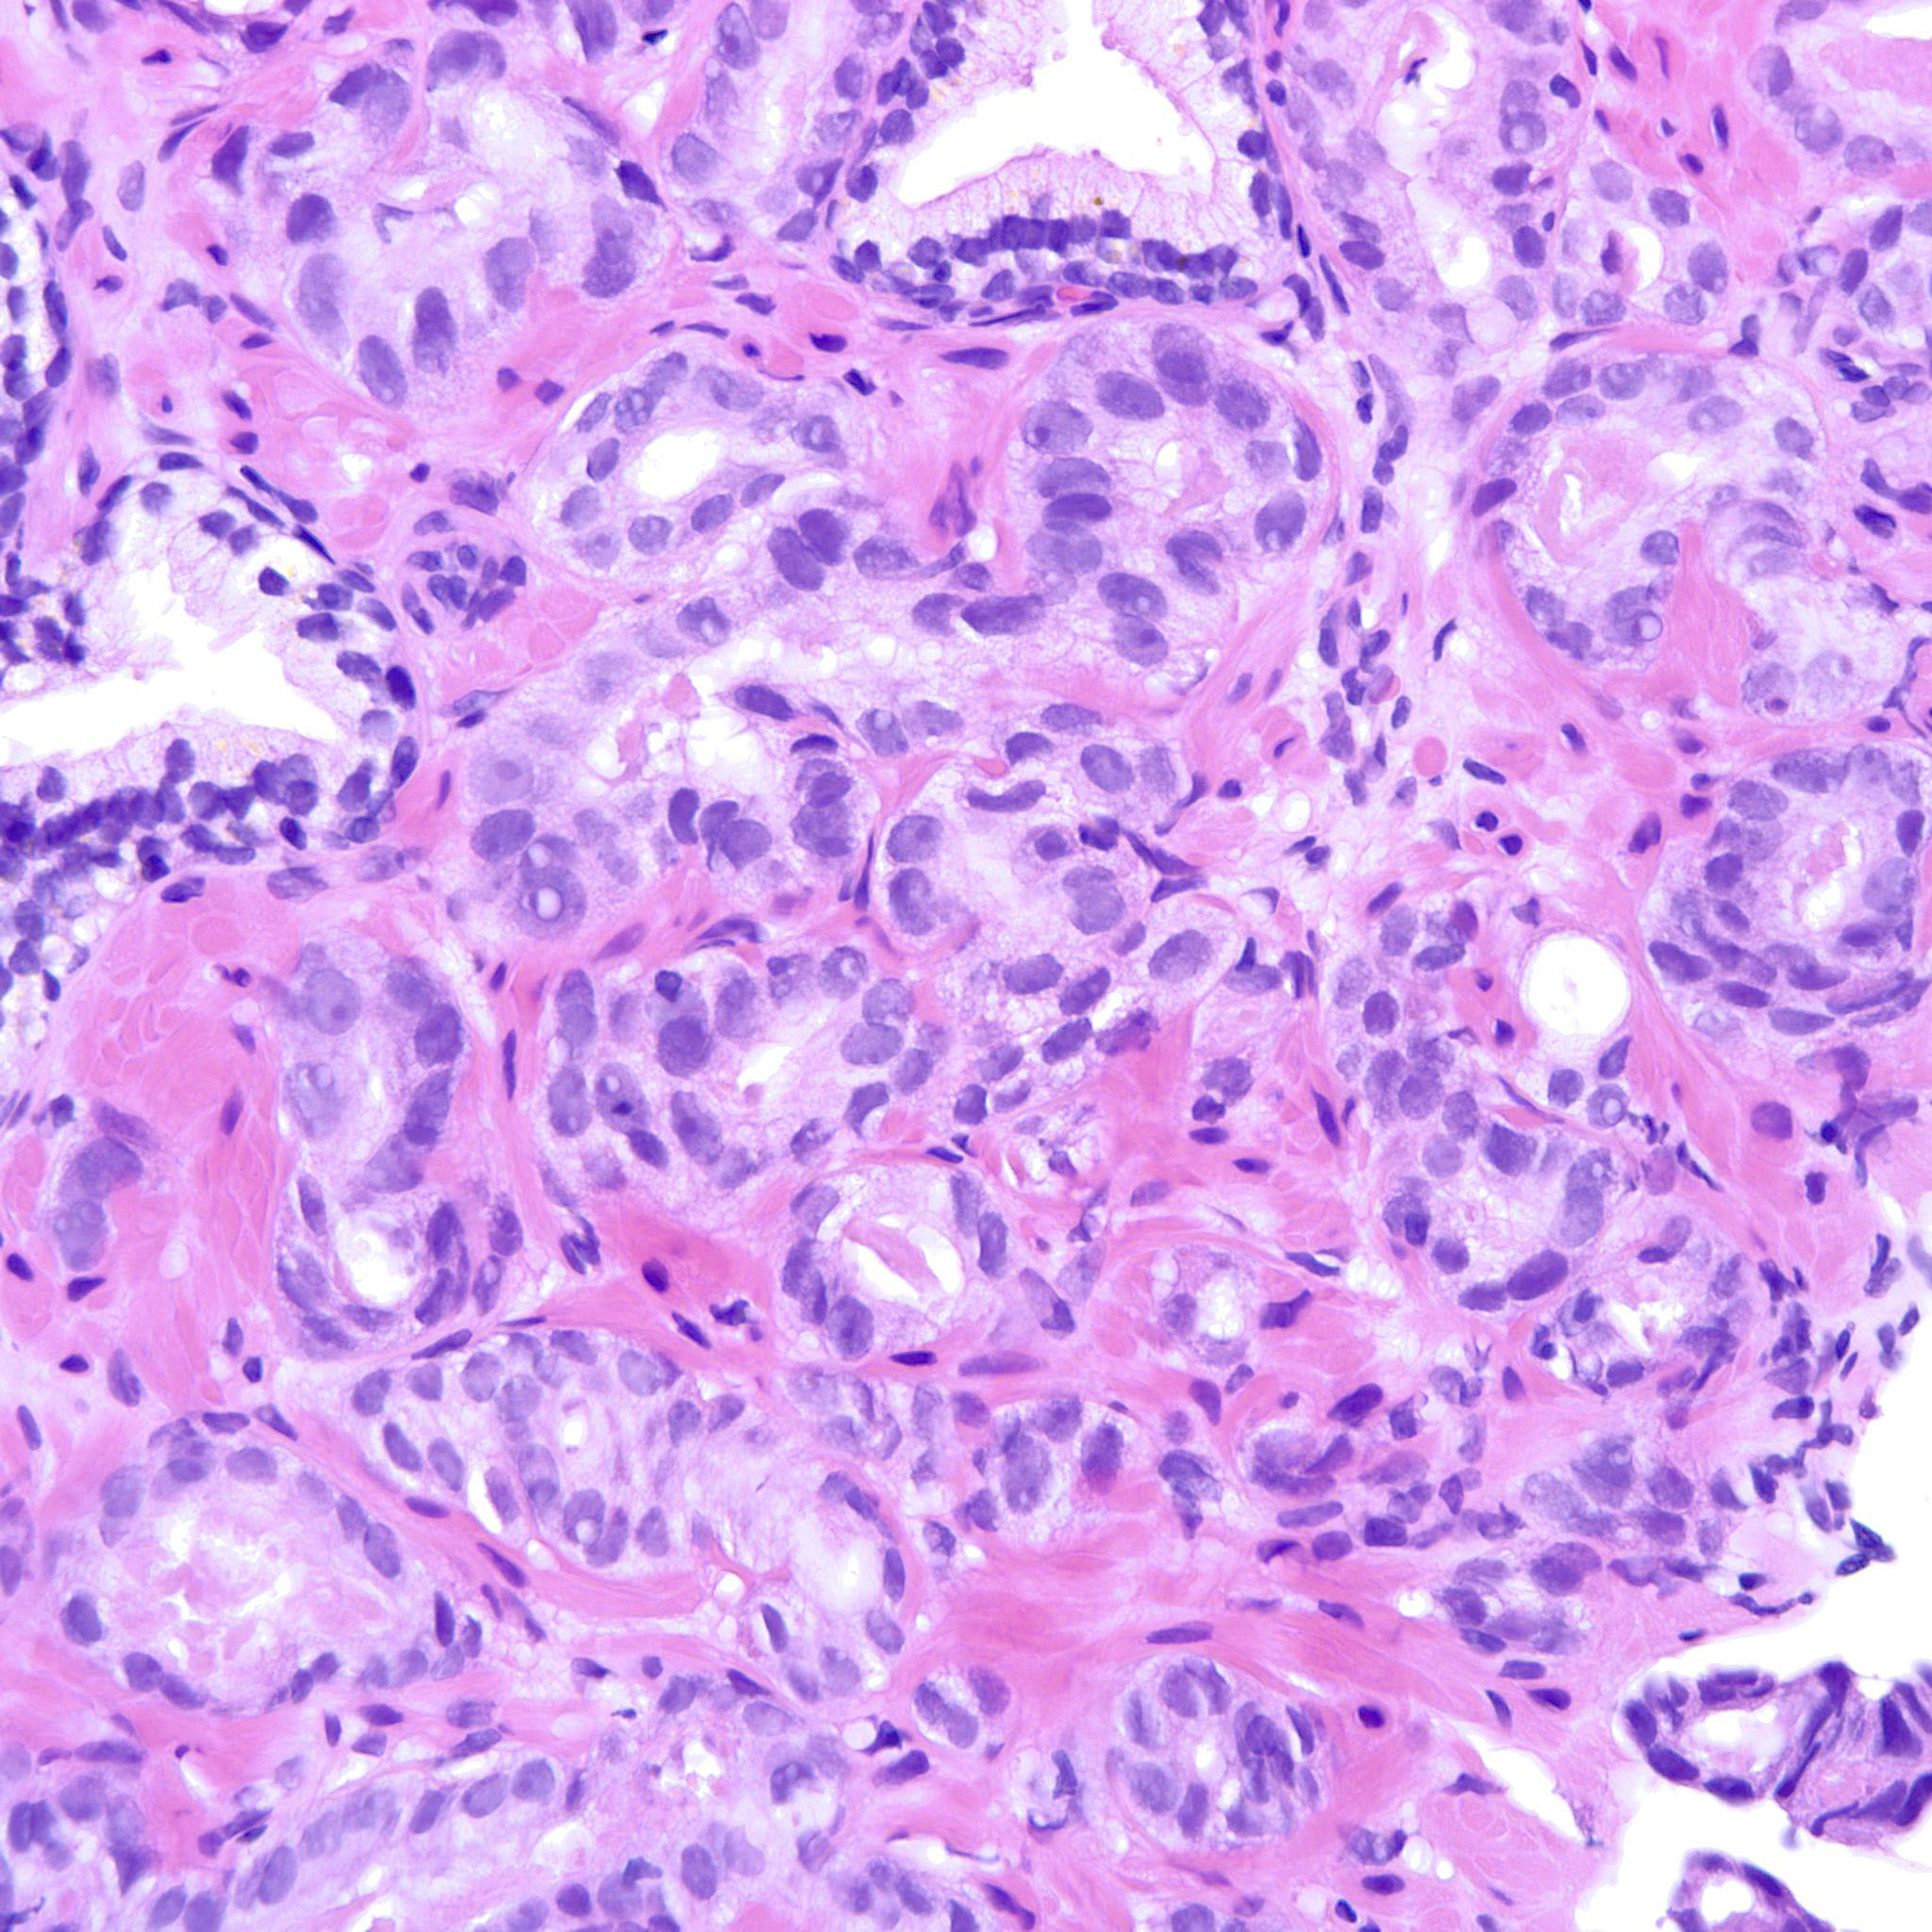

Prostate cancer grading

Case ID: 207